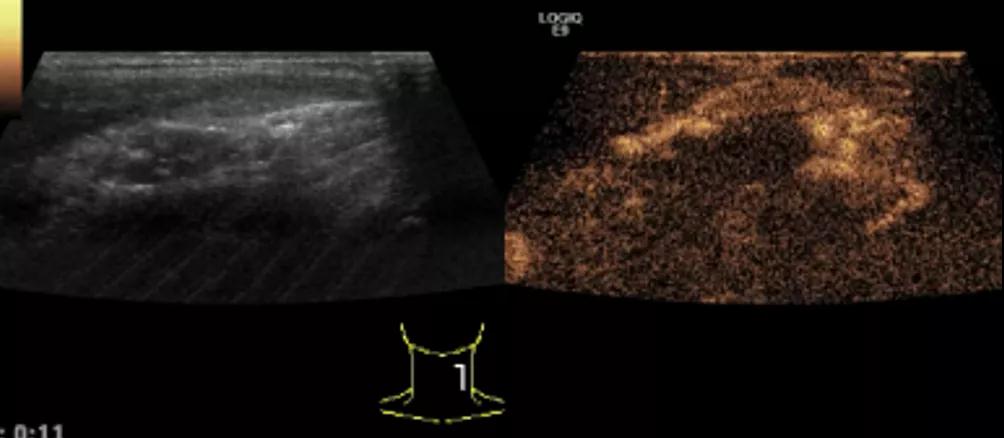

第二例是食管癌患者,术后半年余锁骨上固定淋巴结可触及肿大,疼痛非常明显,系统治疗后无缓解,患者希望通过局部处理缓解症状。造影显示强化信号明显,结节部分区域坏死,故主要针对强化区域从后向前的逐层的消融,皮下进行液体隔离减少烫伤。热消融后影像显示血流增强消失,弹性、硬度增高,一个月后复查显示充盈缺损,完全消融,疗效远超预期。

(病例2图例)